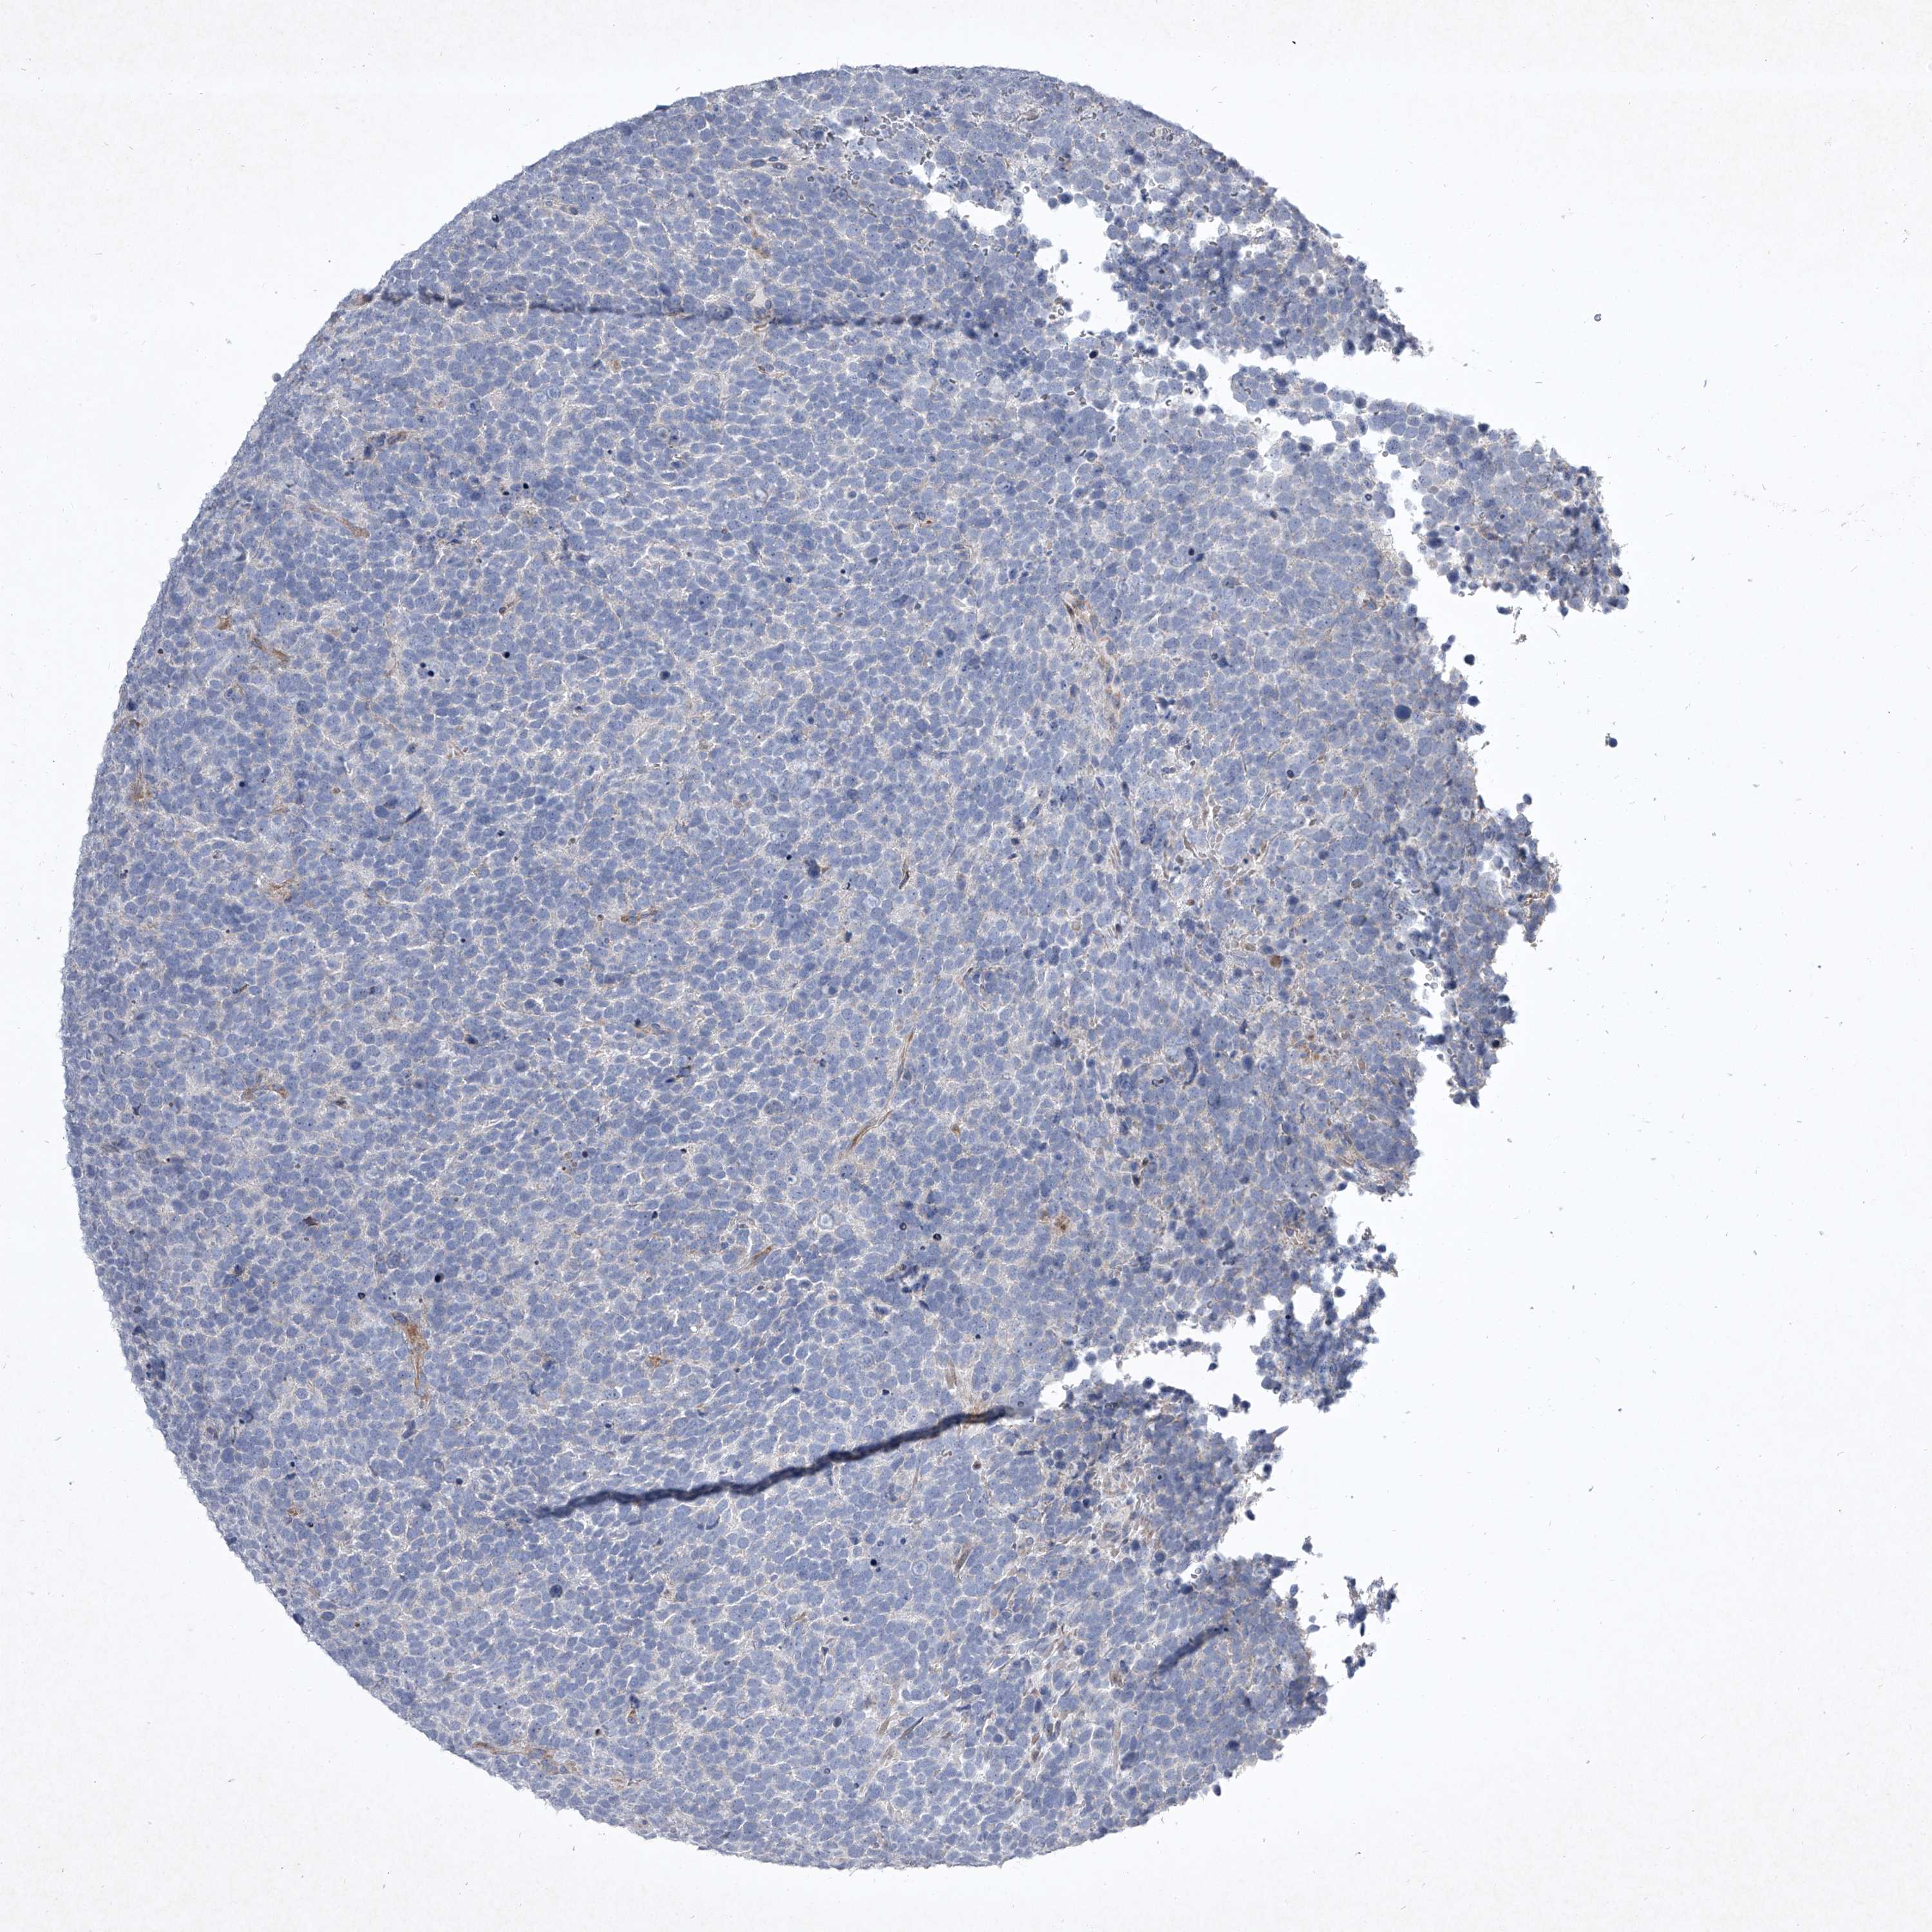

UROTHELIAL CANCER - Protein expressioni

A mouse-over function shows sample information and annotation data. Click on an image to view it in a full screen mode. Samples can be filtered based on level of antibody staining by selecting one or several of the following categories: high, medium, low and not detected. The assay and annotation is described here.

Note that samples used for immunohistochemistry by the Human Protein Atlas do not correspond to samples in the TCGA dataset.

Antibody stainingi

Antibody staining in the annotated cell types in the current human tissue is reported as not detected, low, medium, or high, based on conventional immunohistochemistry profiling in selected tissues. This score is based on the combination of the staining intensity and fraction of stained cells.

Each image is clickable and will lead to virtual microscopy that enables deeper exploration of all samples and also displays staining intensity scores, fraction scores and subcellular localization as well as patient and tissue information for each sample.

Antibody CAB034059

Urothelial carcinoma, Low grade

Urothelial carcinoma, High grade